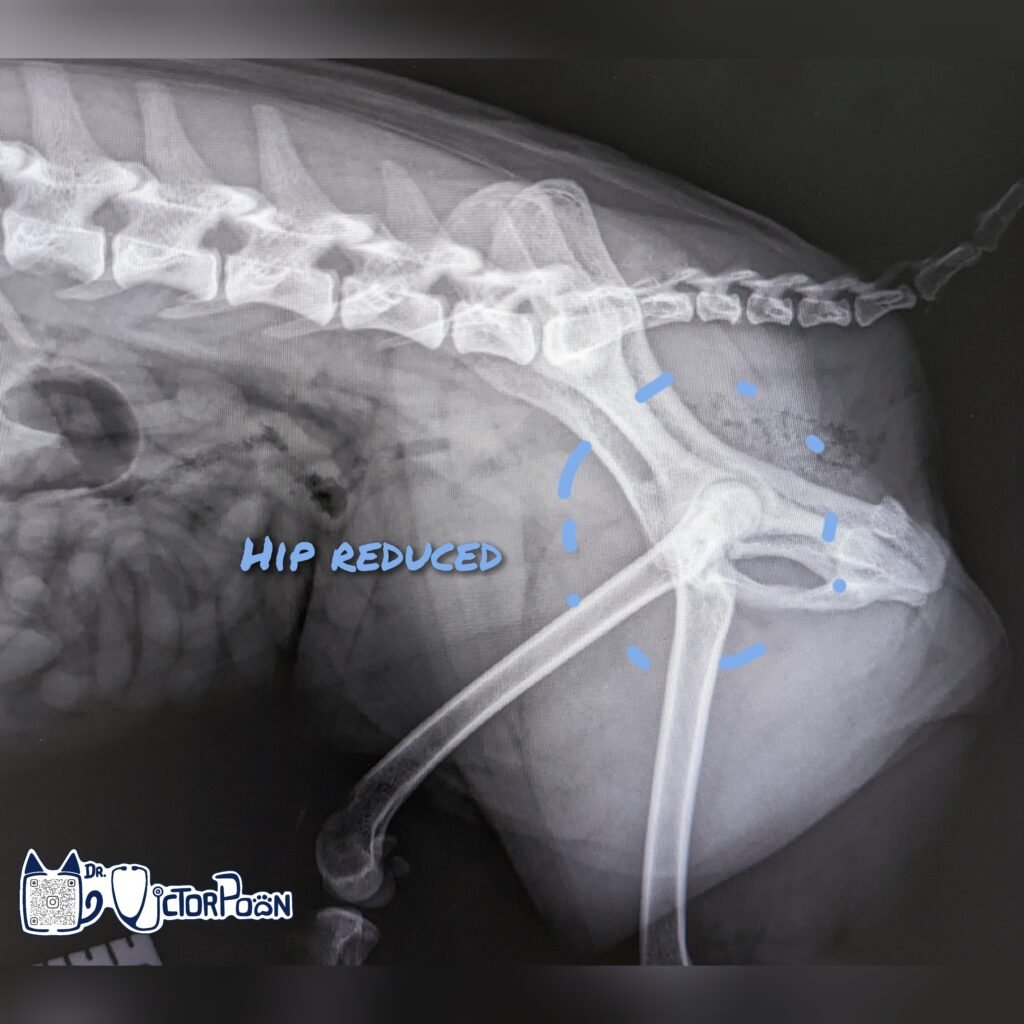

Treatment involves closed reduction under general anesthesia. After successful closed reduction (femoral head returned to its normal location), immobilization of the hip with strict cage confinement +/- bandage is recommended so that fibrous healing of damaged soft tissues can occur. If conservative treatment fails, then surgical options can be considered.